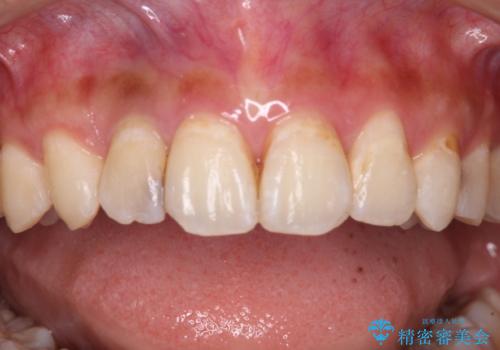

以前治療した前歯をきれいに治したい オールセラミッククラウン

- 根管治療はやり直さずに、ファイバーポストを使用した土台を植立して、オールセラミッククラウンにて補綴することとしました。

神経を取り除いた歯の変色は、クリーニングやホワイトニングでは改善できないため、オールセラミッククラウンなどによる補綴治療が必要となります。